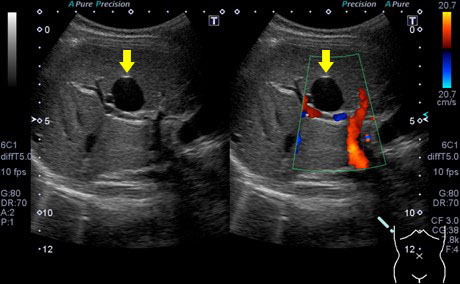

肝嚢胞の診断には腹部超音波検査がもっとも有用で、境界明瞭・内部が無エコー・後方エコー増強といった特徴的な所見を示します。

肝嚢胞の超音波画像:黄矢印

右:パワードプラ(血流のある部位は赤色や青色に表示される)で血流を認めず